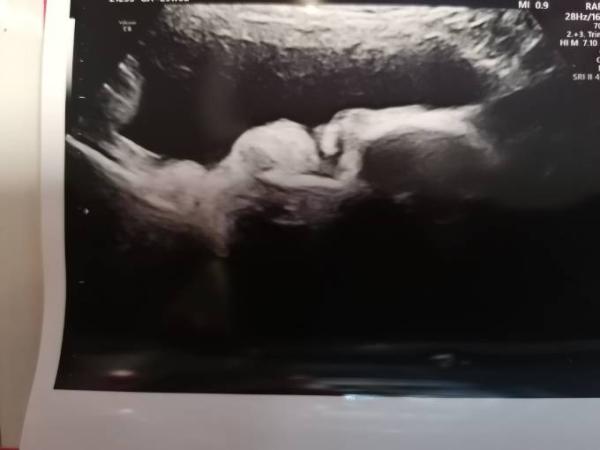

Hallo Mädels, ich hab mal ne seltsame Frage, und zwar war ich gestern noch mal bei der feindiagnostik. Habe zwei bildchen mitbekommen. Hab sie mir aber erst zu Hause wirklich angeschaut. Das eine Bild ist klar, das Profil vom Gesicht meiner püppi. Aber das andere???? Ich habe wirklich keine Ahnung, aber vielleicht eine von euch.

Bild zu Rätselraten - Forum für August - Mamis

Hallo Habe mir das Bild gestern schon einmal angesehen und kann auch beim besten Willen nicht sagen was es nun darstellen soll. Aber mal was anderes. Hat der Arzt bei der Feindiagnostik nicht mit dir geredet, oder dir gesagt was er da "fotografiert"? Meine FÄ klärt mich immer auf, weil ich ultraschallblind bin , und druckt es mir dann aus. Ich weiß also immer, was ich mir da gerade anschaue. Evtl kannst du ja bei deinem nächsten regulären Termin beim FA nachfragen, um was es sich da handelt. Schönes Wochenende.

Meine Vermutung ist, dass sie mir das versehentlich mit ausgedruckt hat. Das war auch mein Plan meine FÄ zu fragen, hoffe sie kann mich aufklären Aber sowas macht mich bissl wahnsinnig, weil ich ja doch etwas neugierig bin Also noch 3 Wochen warten